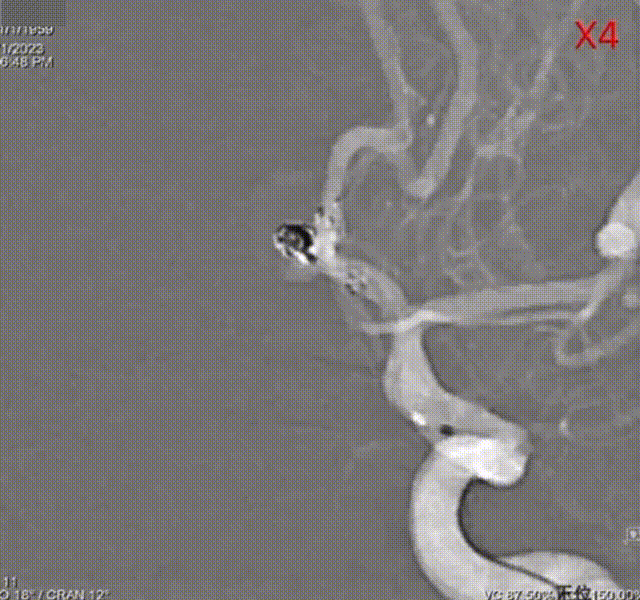

弹簧圈导管重新进入动脉瘤腔,并填入弹簧圈2mm*3cm 3D成篮 。

通过支架导管释放4.5*14mm 闭环雕刻辅助支架覆盖瘤颈。

继续填入1mm*2cm 3D弹簧圈两枚。

DCwire™微导丝保护下撤回弹簧圈微导管。

术后造影及三维重建。